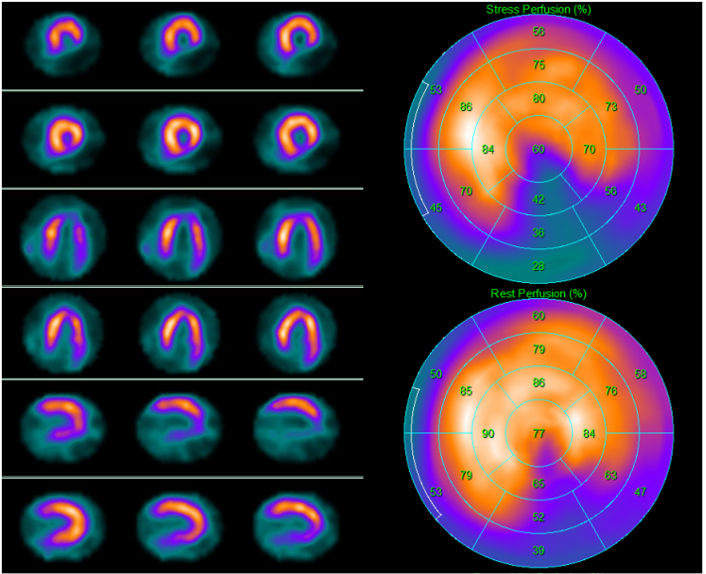

CAD is a major contributor to heart failure worldwide [75]. Tests detecting CAD help clinicians understand the etiology of heart failure and guide patient management in relation to symptoms and prognosis improvement (COR IIa, LOE B) [76]. New or worsening symptoms of heart failure may be associated with myocardial ischemia (Fig. 5). Severely dysfunctional but viable myocardium (hibernating myocardium) is associated with poor outcome, but appropriate revascularization may ameliorate the prognosis [77, 78, 79]. The recently published results of the Surgical Treatment for Ischemic Heart Failure Extension Study (STICHES) showed that patients with ischemic heart disease who underwent CABG surgery had a better prognosis than those who received medical therapy alone at 10-year follow-up [80]. Stress imaging (SPECT or positron-emission-tomography [PET], stress echocardiography, cardiac magnetic resonance) may be considered in patients with CAD who are eligible for coronary revascularization in which the aim should be the detection of myocardial ischemia and viability (COR IIb, LOE B) [76, 81]. Debate continues to surround the management of ischemic left ventricular dysfunction because ischemia, hibernation, viability, scar, and remodeling are variably involved, and it is unclear how to identify the patients who may gain benefit from revascularization in terms of prognosis.

Fig. 5.99mTc-tetrofosmin cardiac single photon emission computed tomography (SPECT) images in a 67-year-old man with dyspnea on exertion and new-onset left ventricular dysfunction with inferior wall akinesia at resting echocardiography. SPECT revealed on the inferior wall a scar due to a previous silent myocardial infarction. Left side top row: stress-rest short axis; stress-rest horizontal long axis; stress-rest vertical long axis; right side: polar map of stress (upper image) and rest perfusion (lower image).